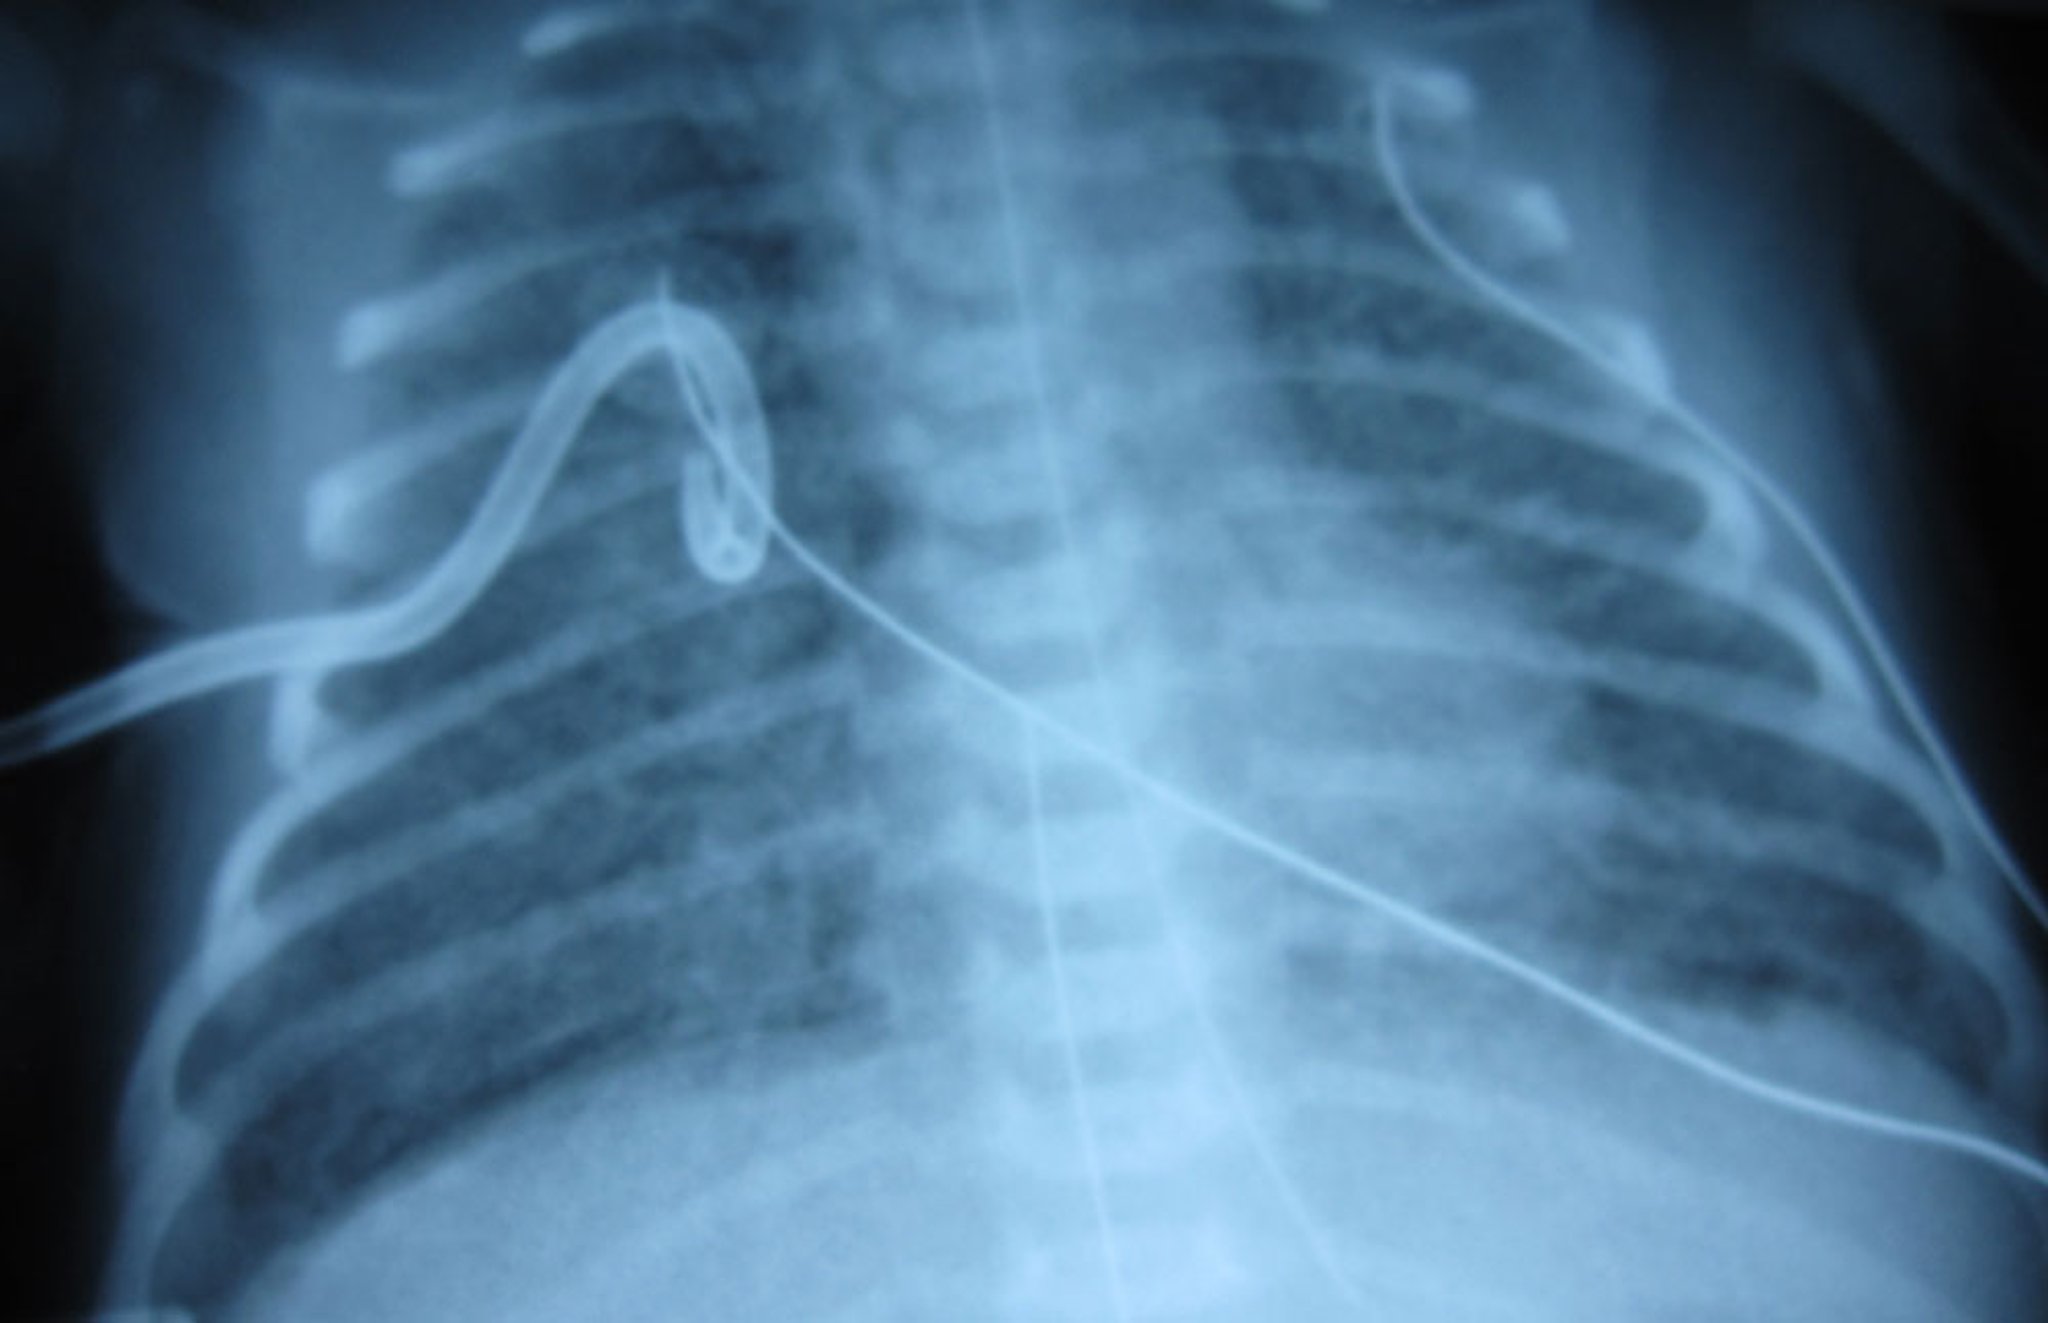

This image shows right-sided tension pneumothorax in a neonate, with visible lung edge and very few pulmonary vascular markings on the right. Tension pneumothorax is a clinical rather than a radiologic diagnosis, but in this image the significant mediastinal shift to the left is highly suggestive of tension pneumothorax.

Image courtesy of Arcangela Balest, MD.